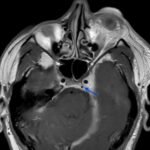

Orbital compartment syndrome (OCS) is an ophthalmologic emergency due to an acute rise in intra-orbital pressure and can result in permanent vision loss, oftentimes requiring emergent surgical decompression. Orbital compartment syndrome most commonly occurs due to recent trauma and is often easily diagnosed by history and physical exam. However, there are other causes of OCS where a more subacute/chronic rise in pressure can lead to an atypical presentation. This is a case report of a 48-year-old male who presented with left eye pain and swelling for the past 6 months. The patient had seen two ophthalmologists prior to his emergency department (ED) presentation who had prescribed him an antibiotic ointment, oral steroids, and steroid eye drops. The physical exam in the ED was concerning for increased intra-ocular pressure (IOP) and decreased vision. Ophthalmology was consulted and requested magnetic resonance angiography (MRA) to assess a vascular etiology given tortuous retinal vasculature. Emergent surgical decompression was deferred due to chronicity of symptoms, and patient was started on dorzolamide/timolol and brimonidine eye drops as well as intravenous (IV) acetazolamide with subsequent improvement in IOP. Imaging revealed a left carotid-cavernous sinus fistula (CCF), and the patient was admitted to neurosurgery. Patient successfully had an embolization with subsequent normalization of IOP and improvement of symptoms. This case is a good example of how non-traumatic causes of OCS can lead to misdiagnosis and how surgical decompression could potentially be deferred in subacute OCS.